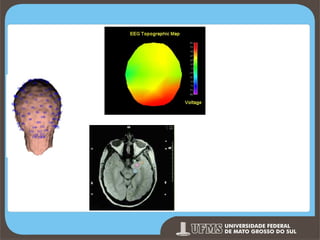

ELETROENCEFALOGRA

MA

Eletroencefalograma

Descoberto por Hans Berger (1929) o EEG consiste no registro da

atividade elétrica do cérebro a partir da fixação de eletrodos na

superfície do couro cabeludo. As anormalidades registradas podem

ser agrupadas em dois conjuntos: 1) distorção, alteração e ausência

de ondas normais e anormais; e, 2) e presença de ritmos anormais

com ou sem alteração da atividade elétrica normal (Selby, 2000).

Os resultados decorrentes da EEG são de utilidade clínica limitada e

reduzido valor para a teorização em neuropsicologia cognitiva.

Eletroencefalogr

ama Topográfico

MRI - Magnetic Resonance

Imaging MEG Magnetoencephalograph